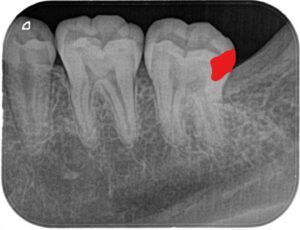

親知らずを抜いた後に小さいX線写真を撮ると第二大臼歯遠心に大きな虫歯がはっきりと写ってきました(下の赤い部分が虫歯です)

一般的には第二大臼歯の咬合面から大きく削り、インレーと呼ばれる詰め物を作ると思います。下の写真のオレンジ色の部分を削るため、虫歯の部分1に対して健康な部分を2~3ぐらい削ります。

当院では、顕微鏡や拡大鏡下で、エアスケーラーという器具にEENOボールというチップを付けて虫歯の部分だけを狙い、健康な歯をできる限り削らない治療法も行っております。